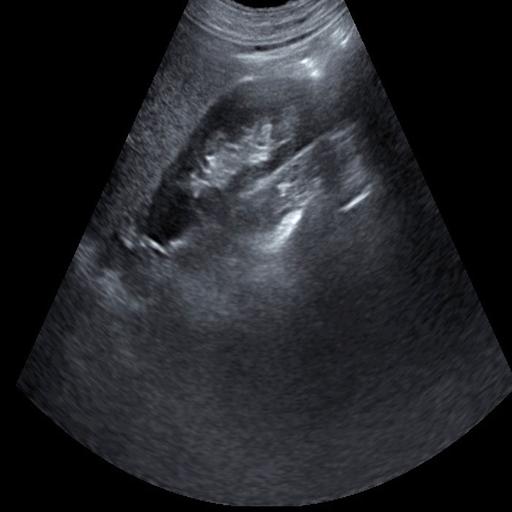

数据样例

结石肾脏样例